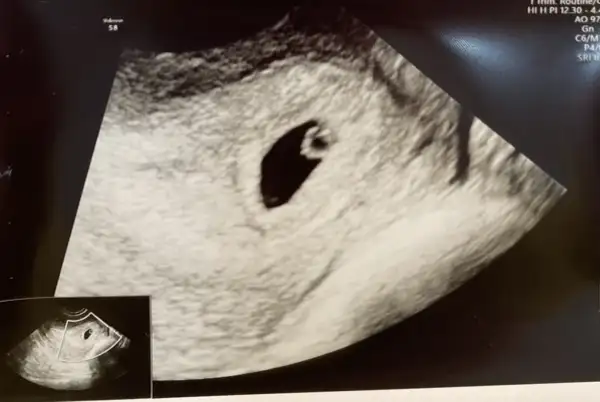

Evet kızlar bugün doktora gittim karından göremedi alttan ultrasonla baktı. Benide yorumlicak var mı

Ay teşekkür ederim doktor bebek gözükmüyor kese ve yolk kesesi mi ne gözüküyor dedi sanırım 2 hafta sonra kalp atışı için çağırdıAyy, canım ne güzel net olarak kesesini ve minik bebişi görmüşsünüz haydi hayırlı olsun